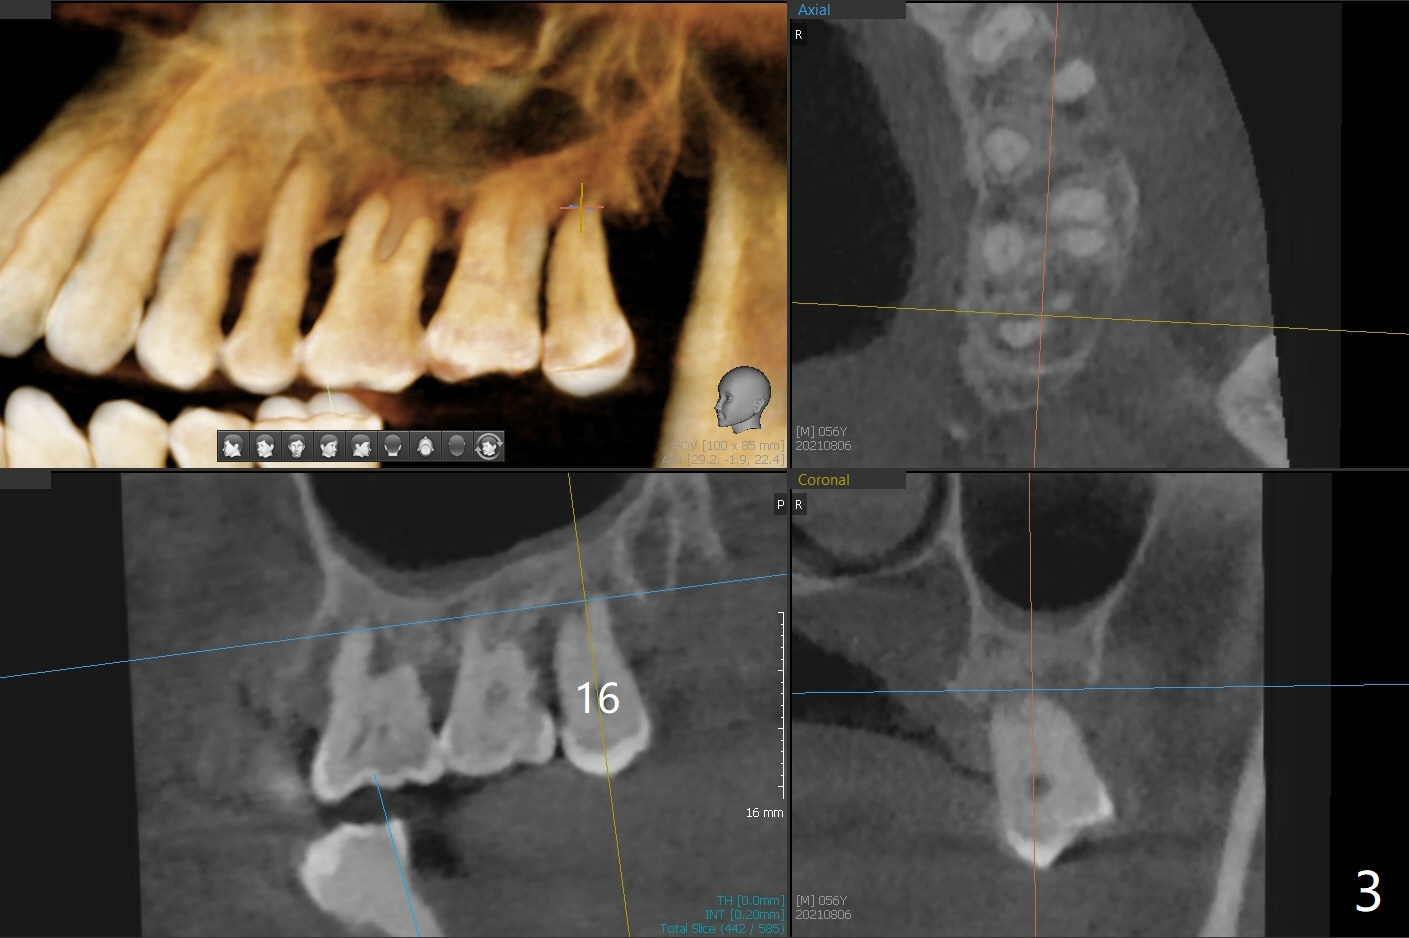

56岁男几十年拒绝牙周炎治疗,也不愿意拔除所有牙齿做全口植牙修复。17,18号牙自行脱落,现在要求拔除16,19;18,19种植(图一),后者牙龈厚(双箭头),但是18号牙骨质高度不足(图二),勉强植入5x7.3毫米植体。15,16骨质吸收严重(图三),16,19拔除,局部深洗后(图四:黑色),为了延长15号牙使用期,16号牙牙槽窝植骨(图五:红色)。19号牙种植徒手,因为邻牙(包括20,21号牙))松动,做导板不准确,钻洞使用环形钻头(图六),保留骨塞(bone plug),用于18号牙骨质高度骨块移植。19号牙拔除后,往远中18牙位做潜行分离(图七:黑色)。19种植(绿色),基台(粉红色),骨粉(圆圈),临时牙冠(白色),16号牙粘性骨粉植骨(红色),PRF,Cytoplast覆盖(白线),缝合。从19号牙钻洞取来的骨塞,塞入18号牙潜行分离处(图八);利用临时牙冠和22号牙以及钢丝,树脂固定20,21号牙(蓝色),并且降低咬合(*)。最后,用螺钉固定骨塞(图九:深蓝色)。